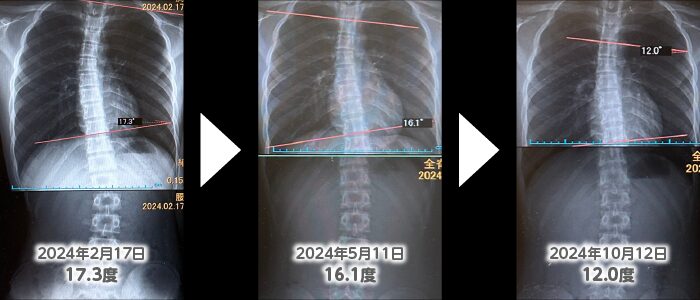

カイロプラクティック治療を受けて、側弯症が改善した臨床例です。14歳(中2)、男性。2024年2月17日、整形外科で思春期側湾症と診断。コルセット不要、経過観察とのことでした。現在、経過観察は継続しているものの、コブ角が8か月で17.3度から12.0度と5.3度改善された臨床例です。*結果には、個人差があります。

お母様からいただいたお声:中学生の息子が軽度の側湾症と診断され経過観察になりました。このまま何もしないでいて良いかな…少しでも良くなればいいな…という思いで、こちらのカイロプラクティックに通うことにしました。徐々に改善していったのには驚きとともに、側湾の改善にともなって、小さい頃からあった頭痛の回数も減り、本当に感謝しております。大切な成長期ですので、引き続き、お世話になりたいと思います。